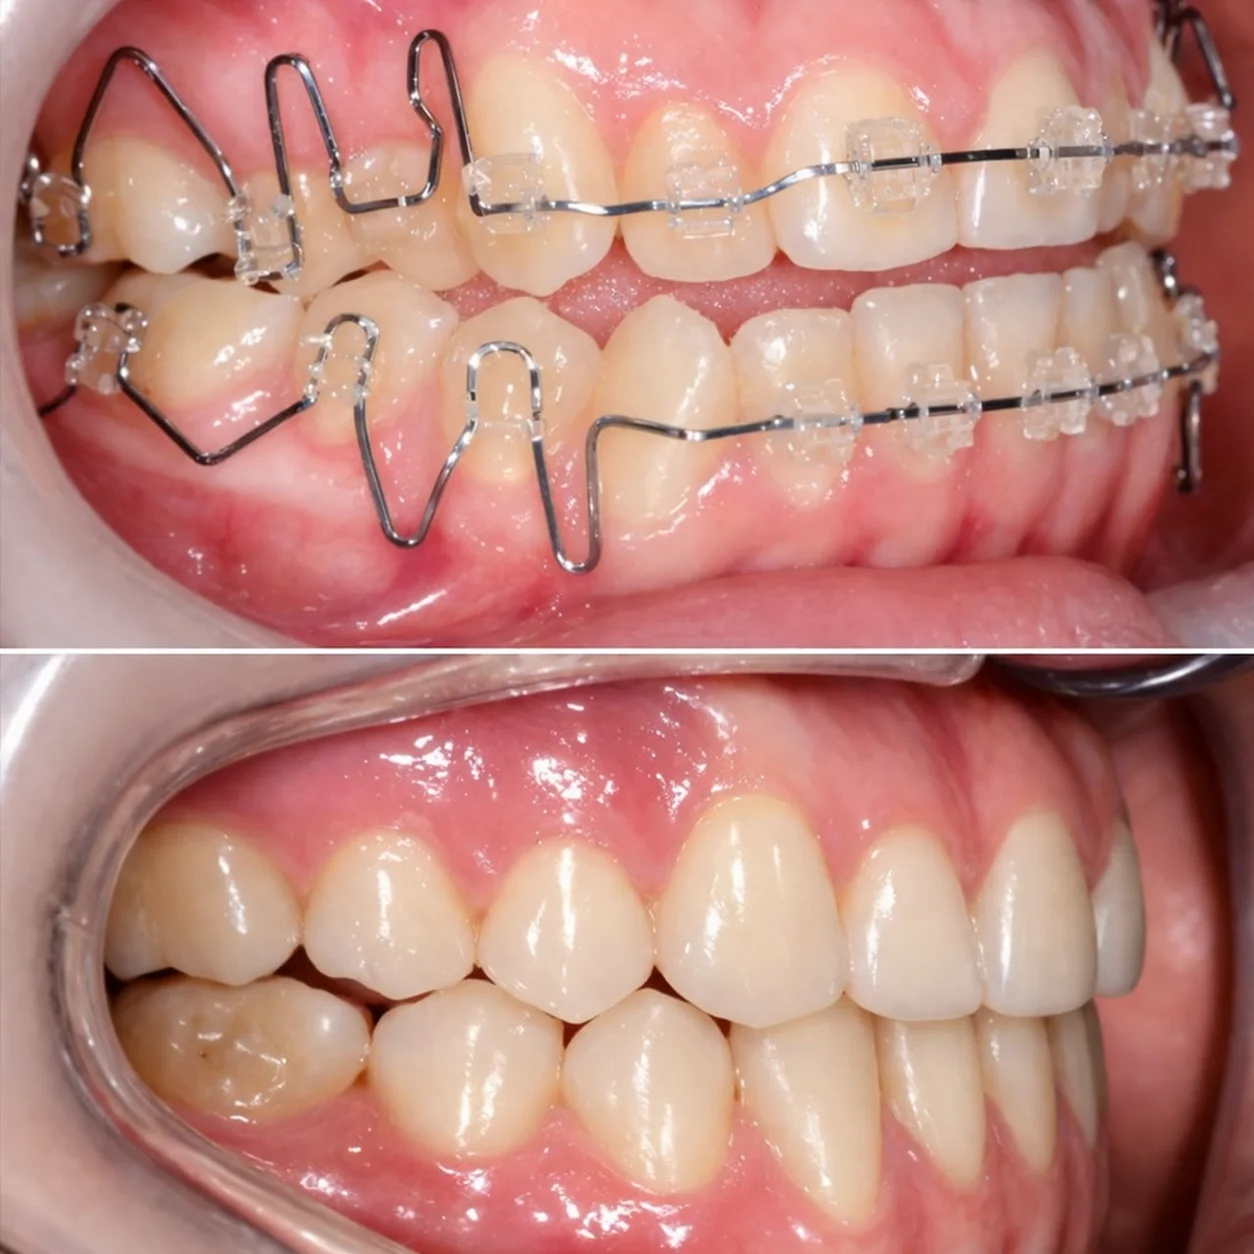

Efekty leczenia

Aparat ortodontyczny

Sięgamy po nie wtedy, gdy potrzebne są poważniejsze zmiany — praca ze zgryzem, stawem i całym układem. Jeśli masz dyskomfort, trzaski w stawie, napięcie mięśni, bóle głowy albo uszu, takie przypadki najlepiej rozwiązywać aparatem